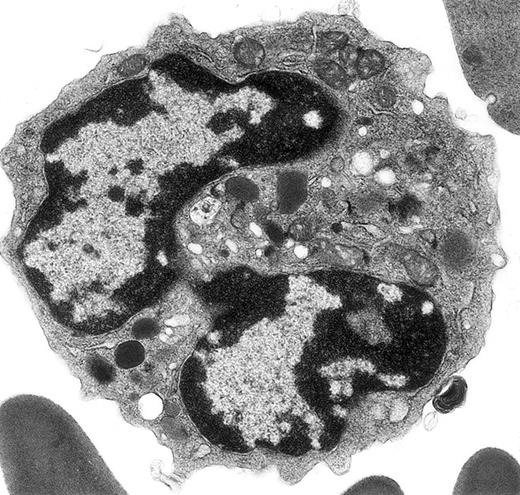

Electron micrograph shows a mature mouse basophil that was present in the FcεR+ cells sorted from normal mouse bone marrow.

(For more details, see Seder et al3and Dvorak et al.4) The mature nucleus has heavily condensed chromatin in 2 lobes. Small numbers of mature electron-dense granules are evident in the cytoplasm. Numerous mitochondria and electron-lucent secretory vesicles constitute the other cytoplasmic organelles in this view. Original magnification, × 23 000.

The mouse basophil lineage was defined by ultrastructural analysis, contrasted with developing mast cell, eosinophil, and neutrophil lineages, and reported in 1982 in this journal.2 These images clearly established the identification and evolution of these lineages in this species and provided the necessary background for the identification of mouse basophils as interleukin-4 (IL-4)–producing, high-affinity FcεR-positive, histamine-containing cells sorted from mouse bone marrow and spleen,3 previously referred to as non-B, non-T cells.10 The ultrastructural characteristics of these basophils are described and contrasted with those of FcεR-positive mast cells and with FcεR-negative neutrophils and eosinophils in detail.4 Further ultrastructural studies with this model revealed that mouse basophils are FcεR-positive and c-kit–negative, whereas mast cells are FcεR-positive and c-kit–positive, and that mouse basophils did not thrive in cultures supplemented with interleukin-3 (IL-3) or stem cell factor (SCF), on the one hand, or with a combination of these 2 mouse mast cell growth factors, on the other.5 In all of these references,2-5 ultrastructural images of mouse basophils identical to the basophil in Verbeek et al's figure 1A-B are included.